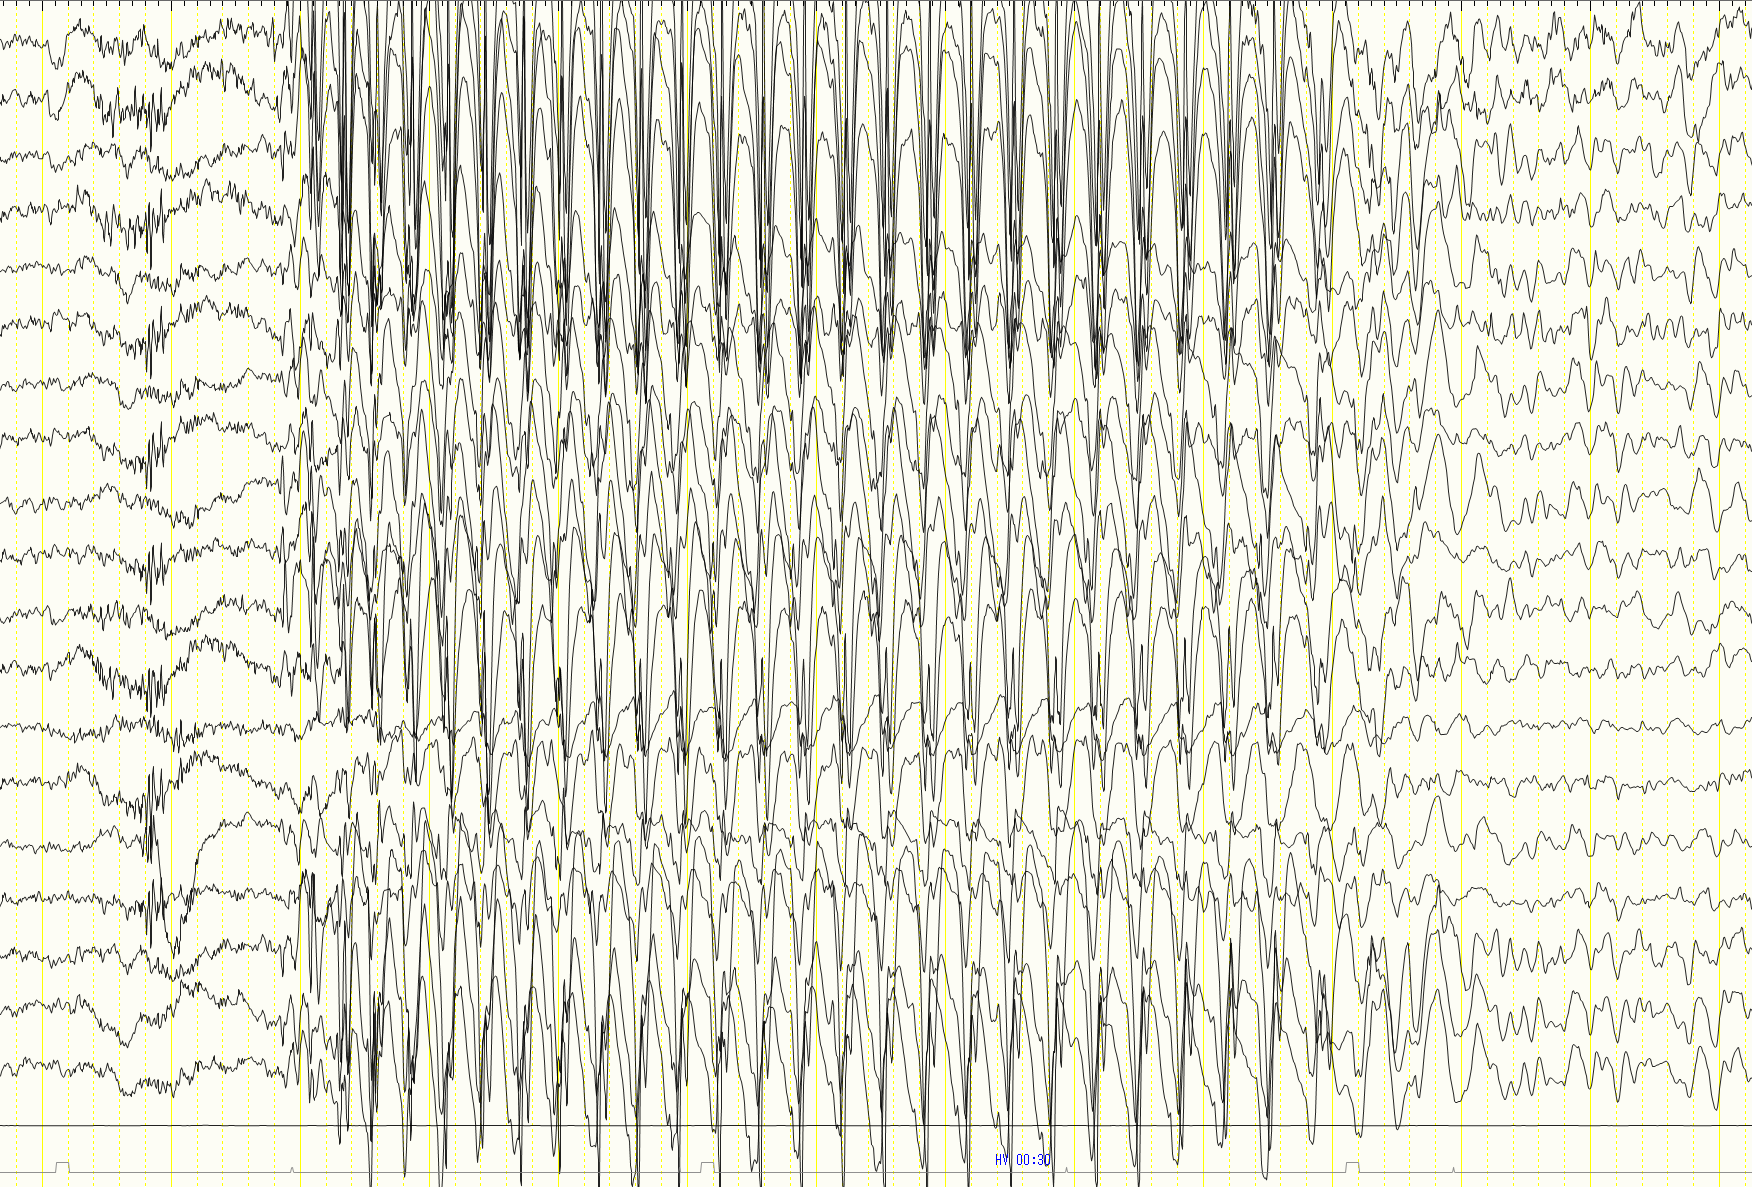

小児欠神てんかんの診断には、詳細な病歴聴取と脳波検査が重要です。 特徴的な3Hz棘徐波複合が脳波で確認されることで診断が確定されます。

特徴的な3Hz棘徐波複合の確認

小児欠神てんかんに特徴的な3Hz棘徐波複合パターン